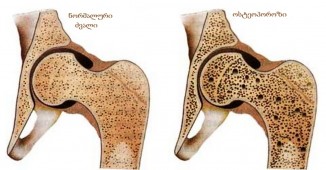

ეს ნებისმიერ ასაკში მნიშვნელოვანია: დაიცავით ძვლები ოსთეოპოროზისგან!

ძვლები იცავს ორგანოებს და აძლევს ძალას კუნთებს. ხშირად გვსმენია, როგორი მნიშვნელოვანია საკმარისი რაოდენობით კალციუმის მიღება ბავშვებისთვის, რათა..